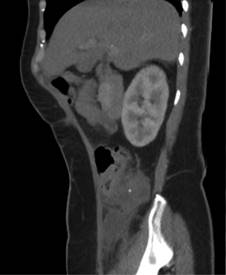

Tomografía simple y contrastada abdominopélvica 03/11/22: colección sub y retrocecal de 50 cm3 con proceso inflamatorio periférico, lo cual sugiere proceso apendicular complicado (Figuras 1 y 2).

Figura 1: Tomografía simple y contrastada de abdomen, corte sagital. En cuadrante inferior derecho con presencia de cambios inflamatorios de la grasa pericecal.

Figura 2: Tomografía simple y contrastada de abdomen, corte coronal. En fosa iliaca derecha se observa imagen circunscrita de densidad cálcica.